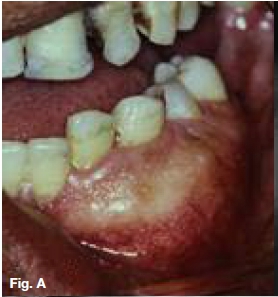

A 30-year old female presented with a swelling extending between 35 and 43, which had grown over the past ten months (Figs.A,B,C), with intermittent pain. Figures D,E,F show a similar case in a 15 year old male patient. Describe the radiological features and list your differential diagnosis.

The cropped pantomograph (Fig.B) shows a multilocular radiolucency of an expansive tumour containing varying calcifications. Figures D&E show a well demarcated multilocular lesion in the body/ramus region of the left mandible, with two displaced molar teeth, resorption of the roots of 34 and 35 and tooth-like calcifications at the borders of the lesion. The coronal T2 MRI image (Fig.F) shows a multilocular hyper-intense lesion, with no discernible calcifications. Diagnosis: the rare tumour, odonto-ameloblastoma (OA), first reported by Kemper and Root (1944). Shafer ef al (1983) described this as an odontogenic neoplasm of mixed tissue origin, consistent with both ameloblastoma and odontoma. Histologically, a typical ameloblastoma component whilst the odontoma element may be either compound or complex. Shafer et al (1983) emphasized that this is one neoplastic process with relatively highly undifferentiated tissues. Occurring most commonly in the second decade of life, it may vary in size. Smaller lesions occur between the teeth, confined to the alveolar bone between the crest of the ridge and the teeth apices (Figs. A,B&C). Buccal expansion of the cortex is common, even for smaller lesions. The odontoma component presents various stages of development, early lesions being radiolucent with radiopaque flecks. More mature lesions are better developed odontoma, resembling teeth or as a nonspecific complex odontoma mass. Importantly, this is an aggressive tumour, treated precisely as an ameloblastoma. The differential diagnosis should include: ameloblastic fibro-odontoma, Pinborg tumour, calcifying odontogenic cyst and adenomatoid odontogenic tumour.